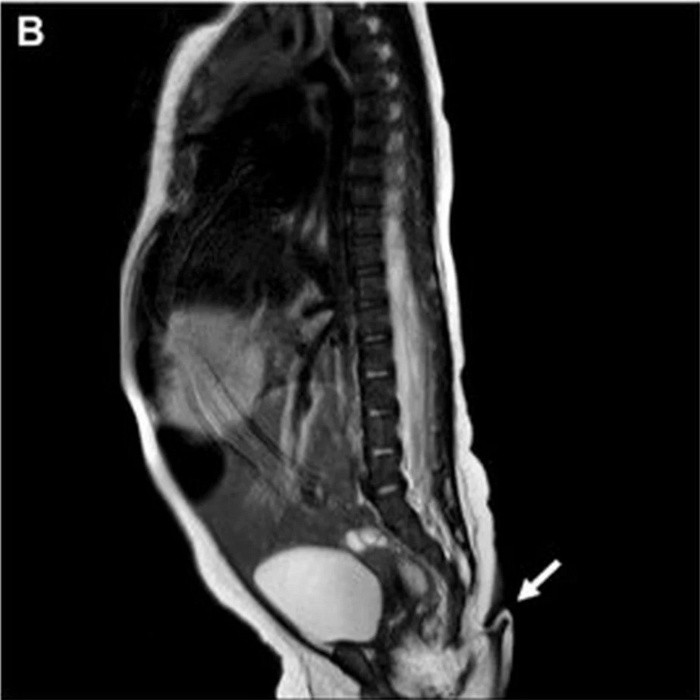

Asimismo, la resonancia magnética practicada no reveló anormalidades cerebrales, además, fue negativa para disrafismo posterior, y presentó médula espinal y cono medular de características normales. Entretanto, la exploración auditiva y cardíaca fue normal, por lo que la pequeña fue dada de alta para seguimiento ambulatorio.